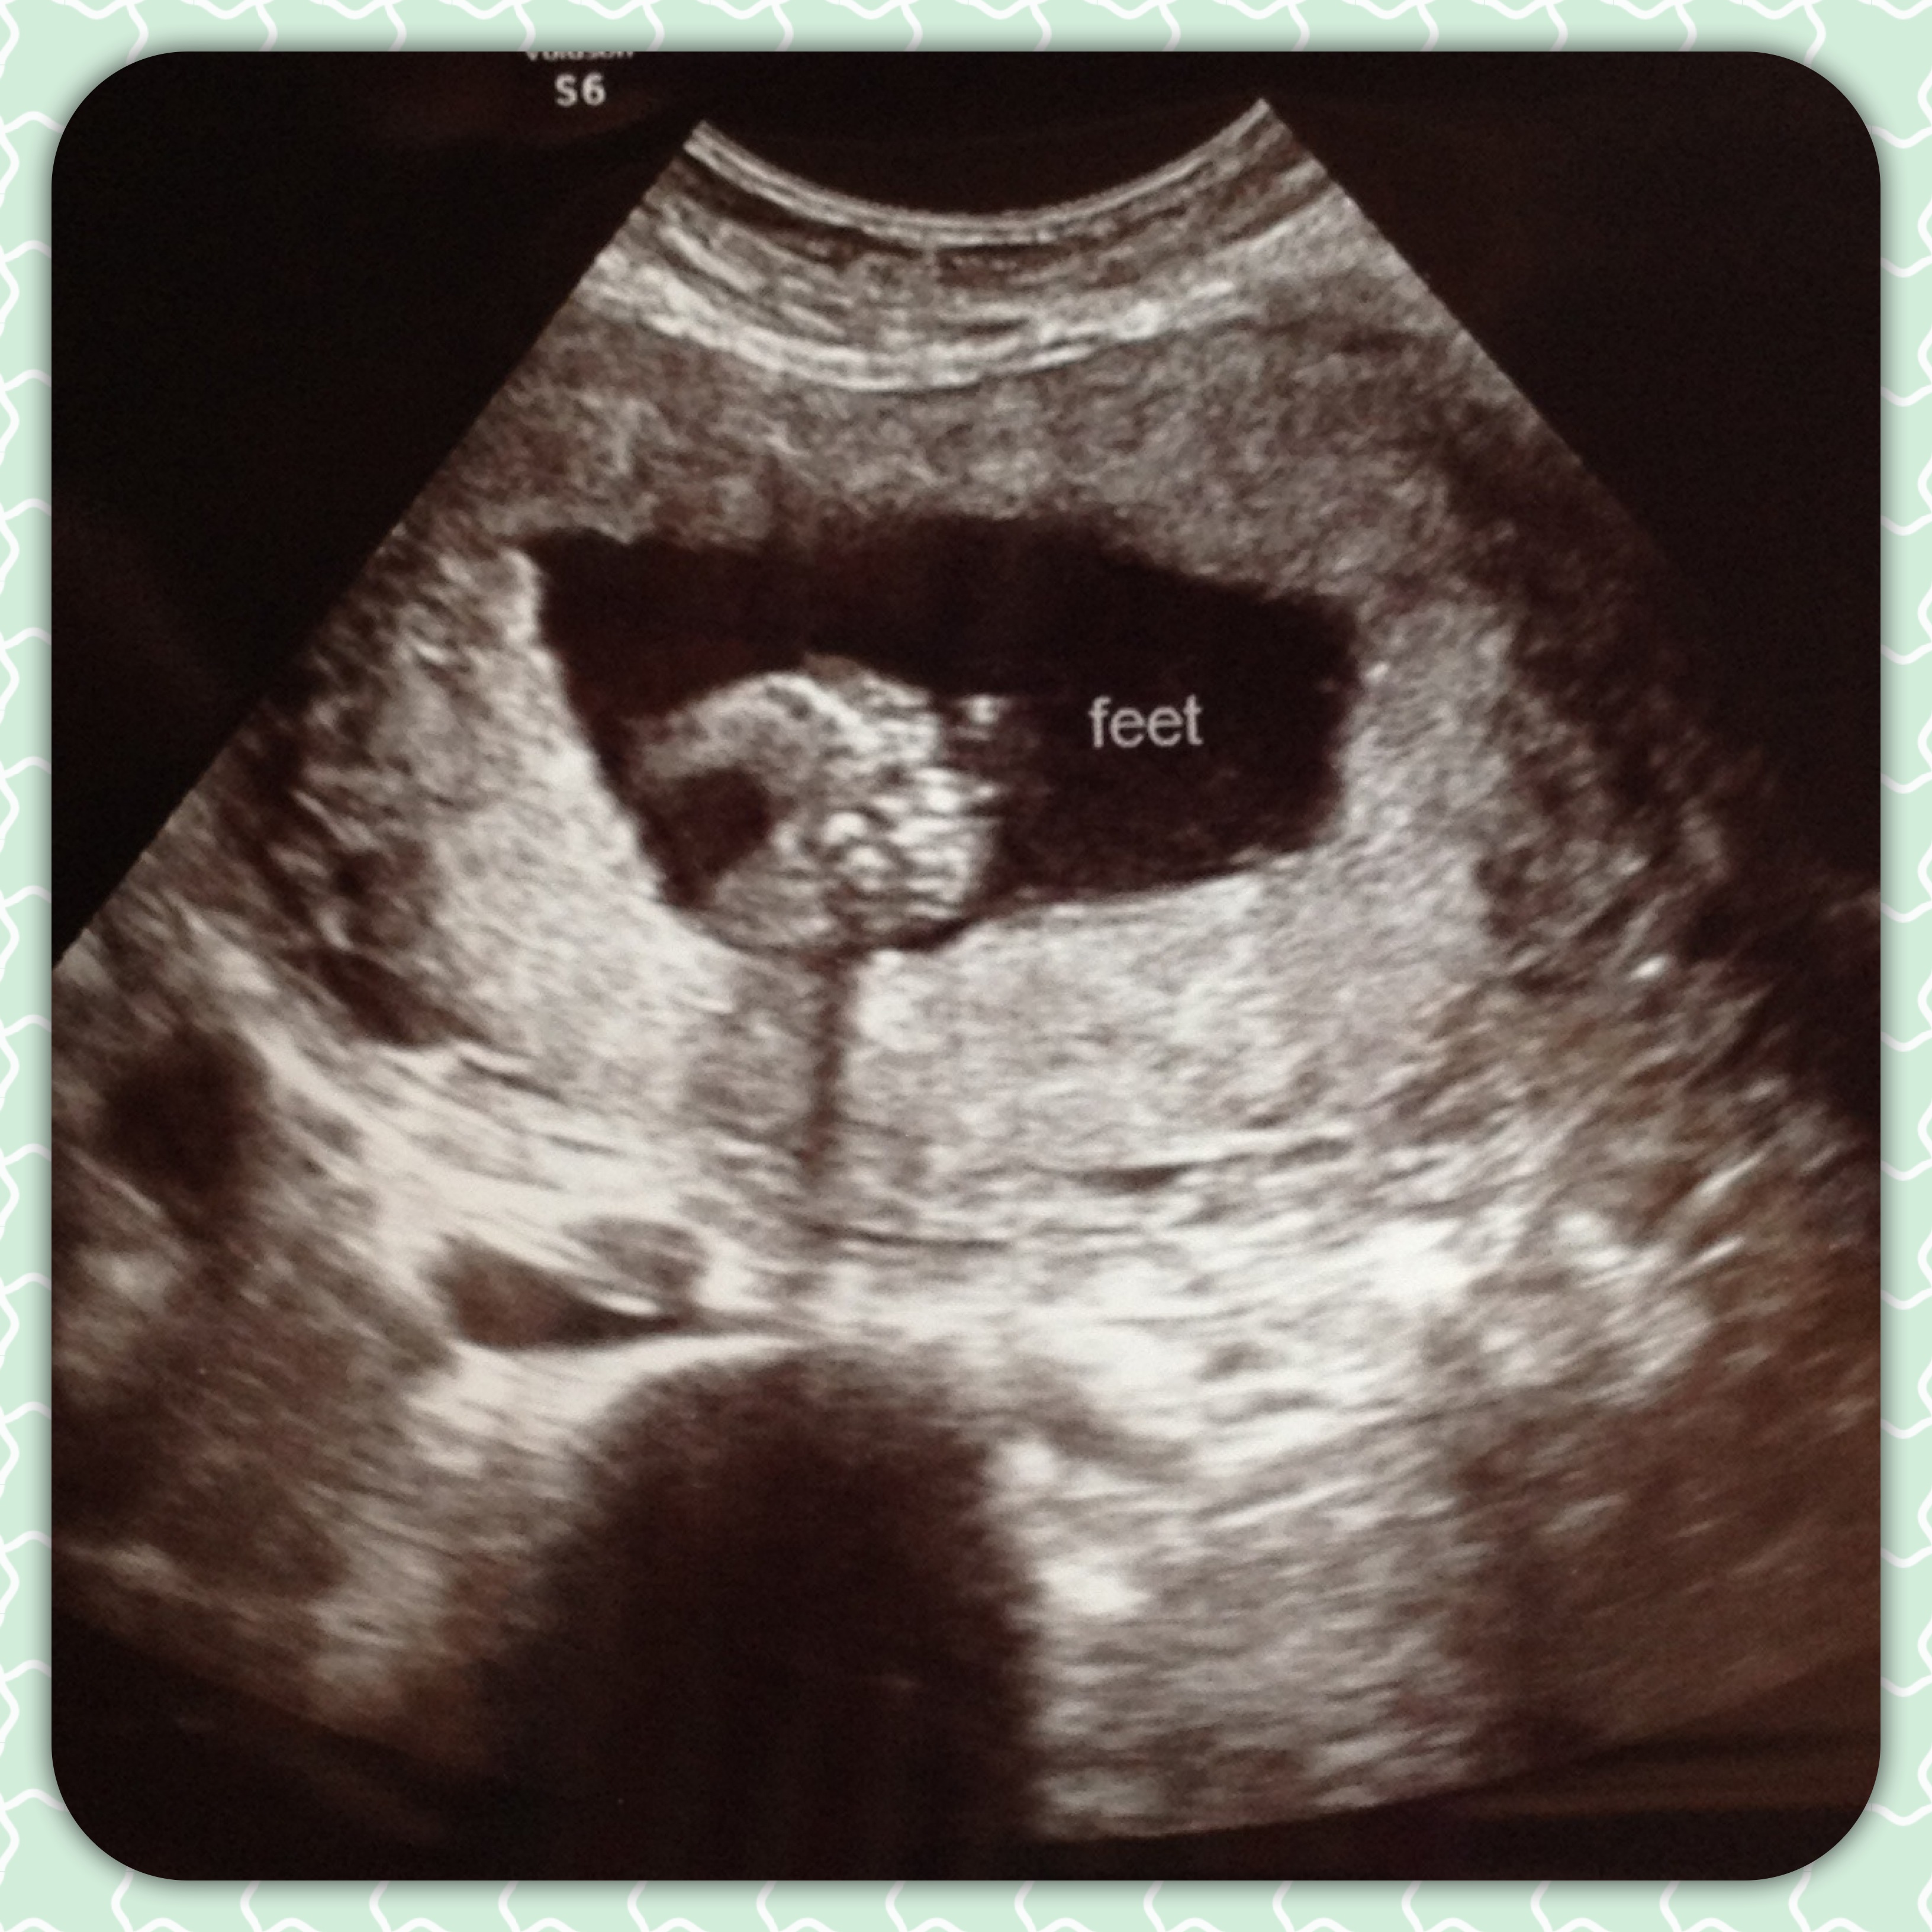

Don’t you think these little feet are cute?